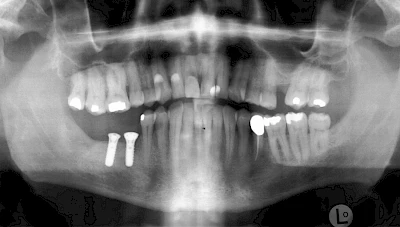

Damit Implantate an der richtigen Stelle im Kieferknochen platziert werden könen, gibt es heute vielfältige Möglichkeiten der Planung. In vielen Situationen kann die Erfahrung des Zahnarztes ausreichend sein.

Nicht selten ist jedoch auch eine technisch aufwändigere Vermessung im Vorfeld sinnvoll, z. B.:

- Wenn sich der Kieferknochen abgebaut hat

- Wenn der Nervverlauf im Unterkiefer beachtet werden muss

- Wenn die Ausdehung der Kieferhöhle im Oberkiefer beachtet werden muss

- Wenn wenige Restzähne keine gute Orientierung erlauben

In diesen Fällen kann die Planung mittels verschieden aufwendiger Röntgen-Techniken (Übersichtsaufnahme, DVT) ggf. unter Zuhilfenahme speziell angefertigter Planungsschablonen sinnvoll sein.